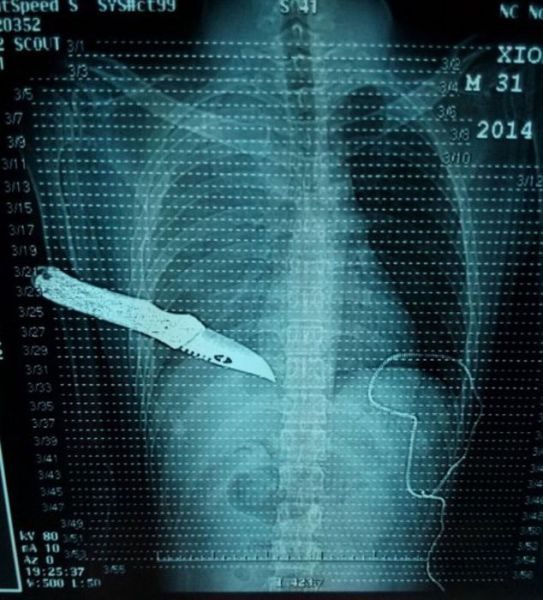

«Бес в ребро», засунул нож